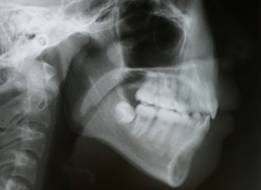

舌を突き出す癖がありました

舌小帯(舌のひも)が長いようです

セファロレントゲン(矯正前)

舌が口蓋につかないので舌小帯の処置をしました

口元が大きく変化しています